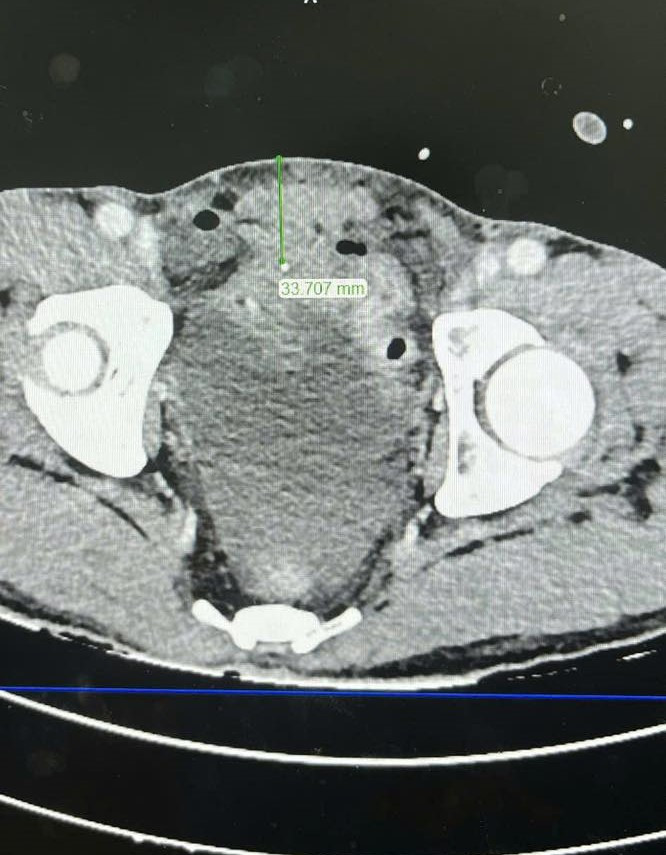

Khi nhập viện, bệnh nhân trong tình trạng đau dữ dội vùng bụng, bụng gồng cứng như gỗ, kèm theo một vết thương nhỏ ở vùng hạ vị. Kết quả chụp CT-Scan bụng cho thấy có dịch và khí tự do trong ổ bụng – dấu hiệu nghi ngờ thủng tạng rỗng.